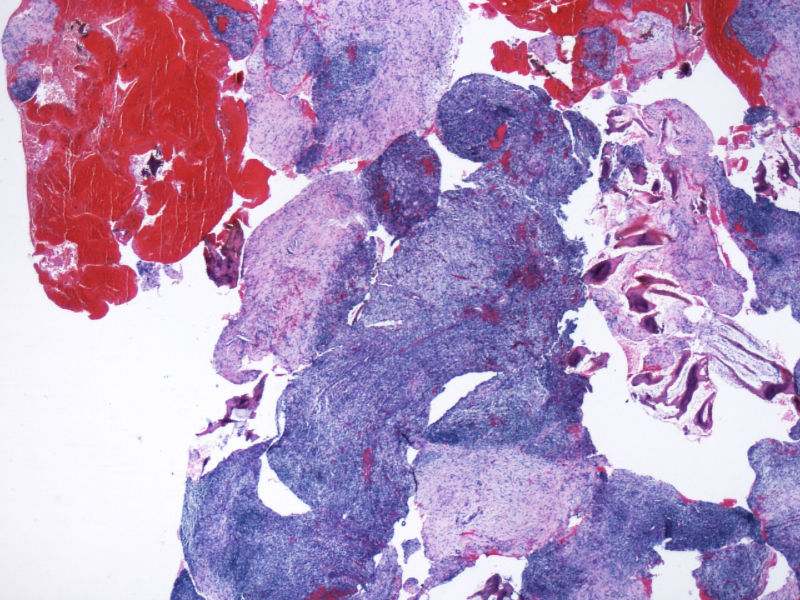

本例患者未查见淋巴结肿大,无肝脾肿大。其余标记物:大细胞显示CD2,CD3,CD4,CD8,CD5,EMA,TIA-1,GranB, oct, Bob1, EBER均阴性。

阳性的有CD30,CD15,CD43,ALK,perforin。

最终诊断为:ALK阳性的间变性大细胞淋巴瘤,淋巴组织细胞变异型。

拿出来的目的:本例始发于骨骼,临床提示脓肿或骨髓瘤,ALK阳性但EMA阴性,细胞毒只有一个标记阳性,本例CD4不阳性。因为CD30和CD15均有非肿瘤细胞阳性的情况,所以对于这个骨骼病例,细胞少而退变,因此最初没有信心诊断,但ALK一般不在非肿瘤细胞内阳性表达,所以最终还是诊断了ALCL。

本例是大细胞病变;本例出现了“裸”免疫表型,这可在ALCL中出现;本例perforin阳性,支持是细胞毒性的大细胞淋巴瘤;大细胞同时表达CD30/CD15/ALK/细胞毒标志物,据目前文献报道,只有ALCL能解释;EBER阴性;临床影像学提示为溶骨性病变。。。